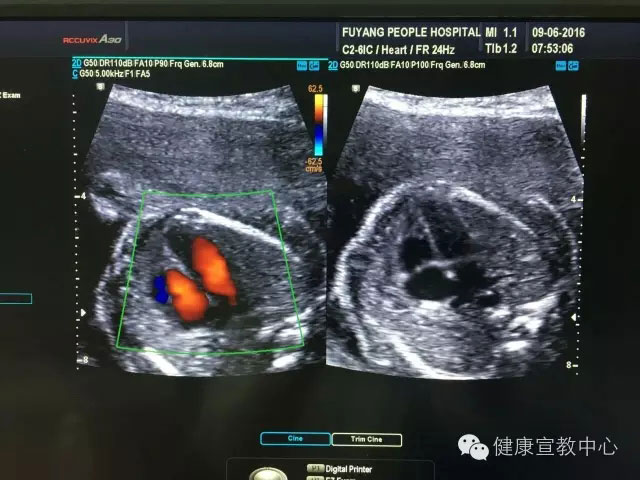

胎兒專項(xiàng)系統(tǒng)檢查是建立在胎兒中孕系統(tǒng)超聲檢查的基礎(chǔ)上對(duì)所篩查的器官、作更系統(tǒng)化精細(xì)化檢查。從2015年,開展胎兒專項(xiàng)系統(tǒng)篩查(胎兒心臟、胎兒中樞神經(jīng)系統(tǒng)、顱腦微小畸形、脊柱等)以來,共計(jì)完成400余例。目前,該項(xiàng)技術(shù)處于省內(nèi)領(lǐng)先水平,部分省級(jí)醫(yī)院還尚未開展。

(胎兒超聲心動(dòng)圖)